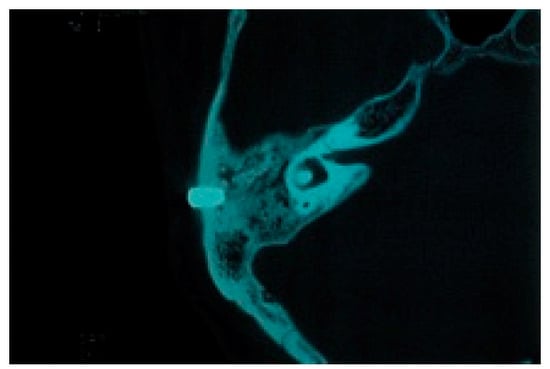

First, the CT data are obtained for use in the imaging anatomical diagnosis and simulation of the drilling positions (Figure 13). With regards to the preoperative simulation, after deciding on the location of the implant site based on the anatomical guidelines in Tjellström et al., one can use the CT images to determine if there is enough thickness to the bone to insert an implant. When planning for a navigation operation, in addition to the above, you will use the computer to create a mirror image of the unaffected ear and place this image on the affected side to get a sense of what the post-operative image may look like. For example, in the case shown in Figure 12, as a decision was already made to use the remaining elongated and deformed ear to surgically create a tragus; the mirroring of the unaffected ear helped select the section of the deformed ear that should be used as the tragus and the section that should be resected (Figure 14). Second, the surgical template with markers is fabricated; a resinous apparatus embedding two implant position markers at the drilling sites and twenty 0.5 mm metallic registration markers on the bar between the ear template and the mouthpiece fitting on the maxillary arch (Figure 15). The CT is taken again with the apparatus attached with three reflective spheres, and the registration is provided on the display (Figure 16). After the confirmation of accurate registration, the ear part of the apparatus is cut before surgery in order to let the implant positions be visible (Figure 17).

There are two main types of navigation systems: optical and magnetic-field type systems. We used the optical navigation system for the sake of convenience as it was pre-loaded in the dental implant software (Artma, Austria) (Figure 18 and Figure 19). However, in a hospital setting, it is possible to use the navigation systems already used by the Department of Neurosurgery or the Department of Otolaryngology or apply the navigation system specifically designed for oral implantations if required. The advantages of using a navigation system along with conventional practice are as follows: the surgeon can verify during the operation, in real time, the drilling direction and its depth within the bone, which is impossible under conventional conditions, and thus avoid damaging vital organs (Figure 20). When the preoperative analysis and the reality differ during the operations, it is possible to reanalyze the images during the operation and change the implantation plan accordingly. By creating a surgical template attached to the maxillary dentition, one can start the preoperative registration without the presence of the patient, which reduces the operation time (Figure 16 and Figure 17). The disadvantage is that there is a slight error margin between the CT and the location information detection system (which is said to be +0.35 mm with the CT slice width with the Artma system, though its competitor systems have a similar range of errors), which means one must gain proficiency in registration.

Figure 20. Navigation during drilling into the temporal bone. The drill (yellow bar) is guided to the expected position and direction (red rod).